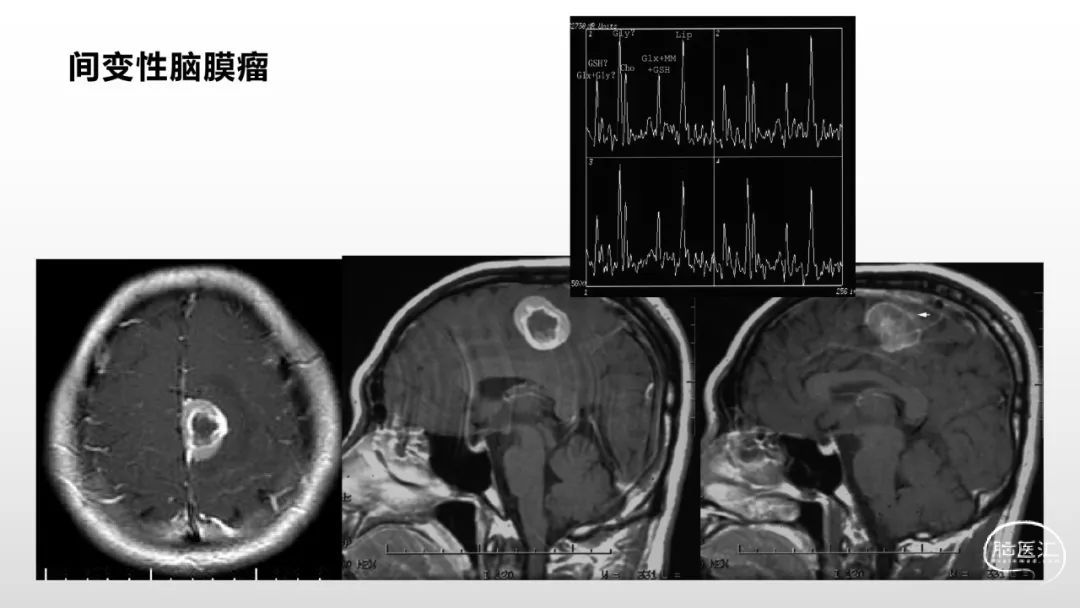

颅脑影像诊断基础知识讲座:脑膜病变